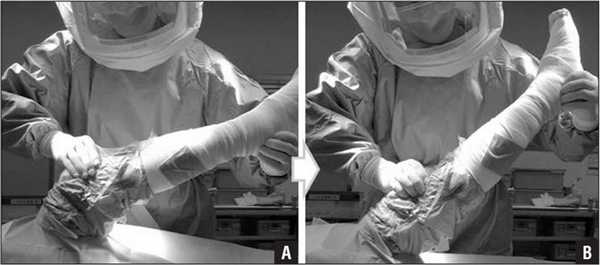

Первые дни ноги туго бинтуют для профилактики тромбофлебита.

Эластичное бинтование

На протяжении 6 недель после выполненной операции есть риск тромбов и отечности. Поэтому специалистом в раннем периоде назначается эластичное бинтование, в более позднем - компрессионные чулки. Степень компрессии данных медицинских изделий подбирает ортопед, учитывая объемы вмешательства и фактор предрасположенности к тромбообразованию. Наложение эластичного бинта и ношение компрессионного белья препятствуют развитию тромбоза глубоких вен.

Бинты используются все реже, они очень плохо держаться при движении. Чаще применяют такой компрессионный трикотаж.

Технике, как бинтовать ногу, вас обучат в стационаре. Сначала бинтование осуществляет врач, а по возвращении домой вам придется это делать самостоятельно. Будьте внимательны ко всему, что говорит и чему учит вас медицинский персонал, пока вы еще находитесь в клинике или реабилитационном центре.